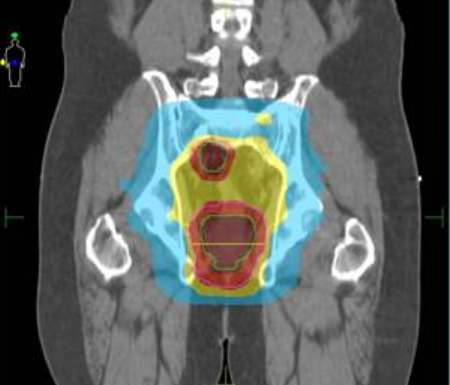

An IMRT dosing plan for an adult with rectal cancer

A dosing plan for intensity modulated radiation therapy in a person with rectal cancer.

Credit: Journal of Cancer. September 2017. doi:10.7150/jca.21237. CC BY-NC 4.0